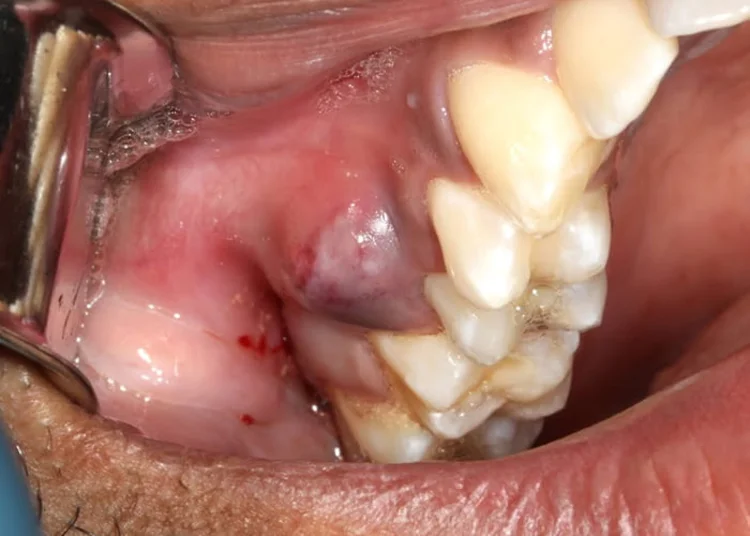

A localized infection may present as a tooth abscess, while more severe cases can spread to surrounding tissues.

- Drainage of infection – If pus is present, relieving pressure is often the first step.

- Surgical intervention – Advanced infections may require incision and drainage under oral surgery.